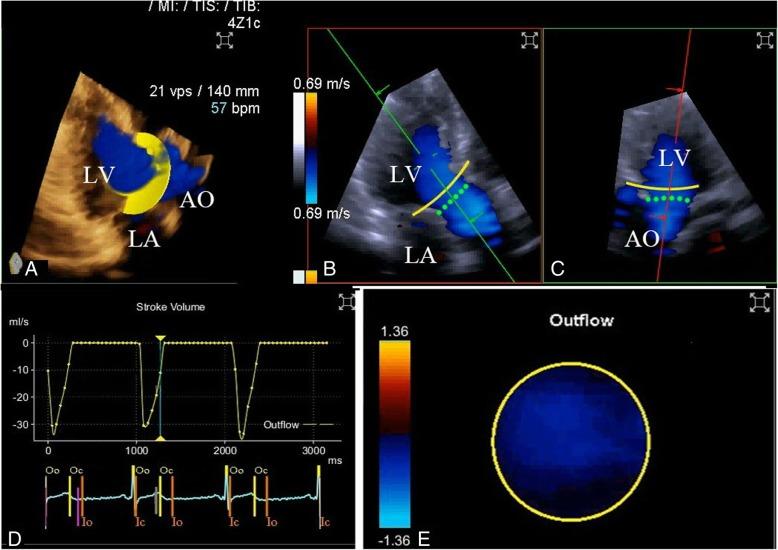

Three-dimensional color flow Doppler (3DCF) is a new convenient technique for cardiac output (CO) measurement. However, to date, no one has evaluated the accuracy of 3DCF echocardiography for CO measurement after cardiac surgery. Therefore, this single-center, prospective study was designed to evaluate the reliability of three-dimensional color flow and two-dimensional pulse wave Doppler (2D-PWD) transthoracic echocardiography for estimating cardiac output after cardiac surgery.

Post-cardiac surgical patients with a good acoustic window and a low dose or no dose of vasoactive drugs (norepinephrine < 0.05 μg/kg/min) were enrolled for CO estimation. Three different methods (third generation FloTrac/Vigileo™ [FT/V] system as the reference method, 3DCF, and 2D-PWD) were used to estimate CO before and after interventions (baseline, after volume expansion, and after a dobutamine test).

A total of 20 patients were enrolled in this study, and 59 pairs of CO measurements were collected (one pair was not included because of increasing drainage after the dobutamine test). Pearson's coefficients were 0.260 between the CO-FT/V and CO-PWD measurements and 0.729 between the CO-FT/V and CO-3DCF measurements. Bland-Altman analysis showed the bias between the absolute values of CO-FT/V and CO-PWD measurements was - 0.6 L/min with limits of agreement between - 3.3 L/min and 2.2 L/min, with a percentage error (PE) of 61.3%. The bias between CO-FT/V and CO-3DCF was - 0.14 L/min with limits of agreement between - 1.42 L /min and 1.14 L/min, with a PE of 29.9%. Four-quadrant plot analysis showed the concordance rate between ΔCO-PWD and ΔCO-3FT/V was 93.3%.

In a comparison with the FT/V system, 3DCF transthoracic echocardiography could accurately estimate CO in post-cardiac surgical patients, and the two methods could be considered interchangeable. Although 2D-PWD echocardiography was not as accurate as the 3D technique, its ability to track directional changes was reliable.